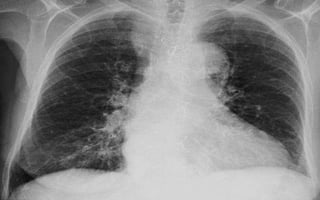

CASOS PATOLOGICOS

1. Aumento del índice

cardiotorácico.

2. APEX se dirige hacia abajo del

diafragma por dilatación delVI.

3. Aumento de la densidad

pulmonar bilateral con

distribución perihiliar y basal,

aspecto algodonoso,

confluente, límites mal

definidos borrosidad vascular

(InfiltradoAlveolar).